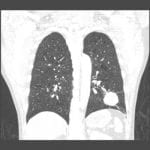

- 4 cm round masslike opacity in the left lower lobe

- Linear opacities in the right midlung

- No pleural effusion or pneumothorax

- Normal size and configuration of the cardiopericardial silhouette

- Adenocarcinoma

4 cm round masslike opacity in the left lower lobe concerning for neoplasm. Recommend chest CT for further evaluation.

Linear opacities in the right midlung likely represent atelectasis or scarring.